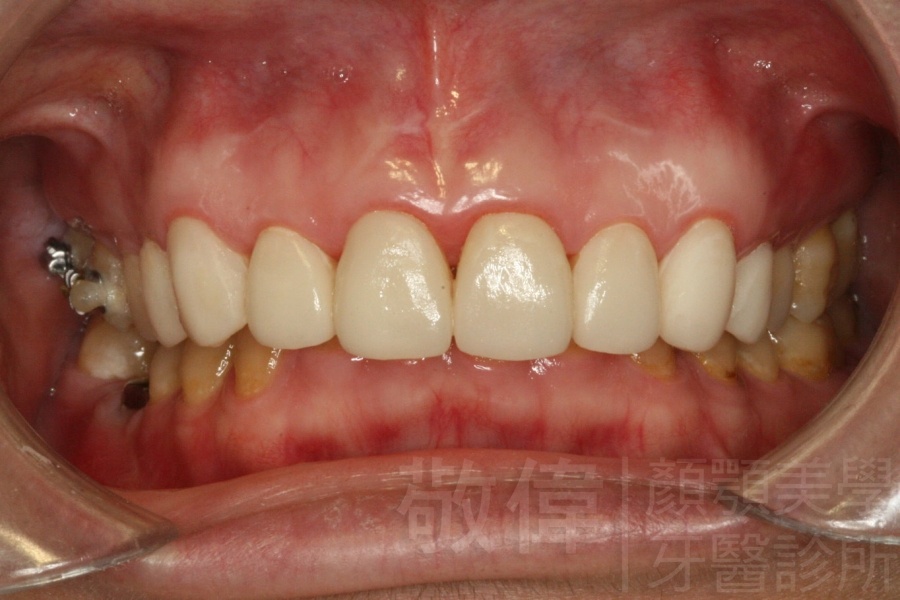

| 6 | 前牙美容 | 矯正+牙齦增補+晶鑽全瓷冠 | ||

| 7 | 前牙美容 | 矯正+晶鑽全瓷冠 | ||